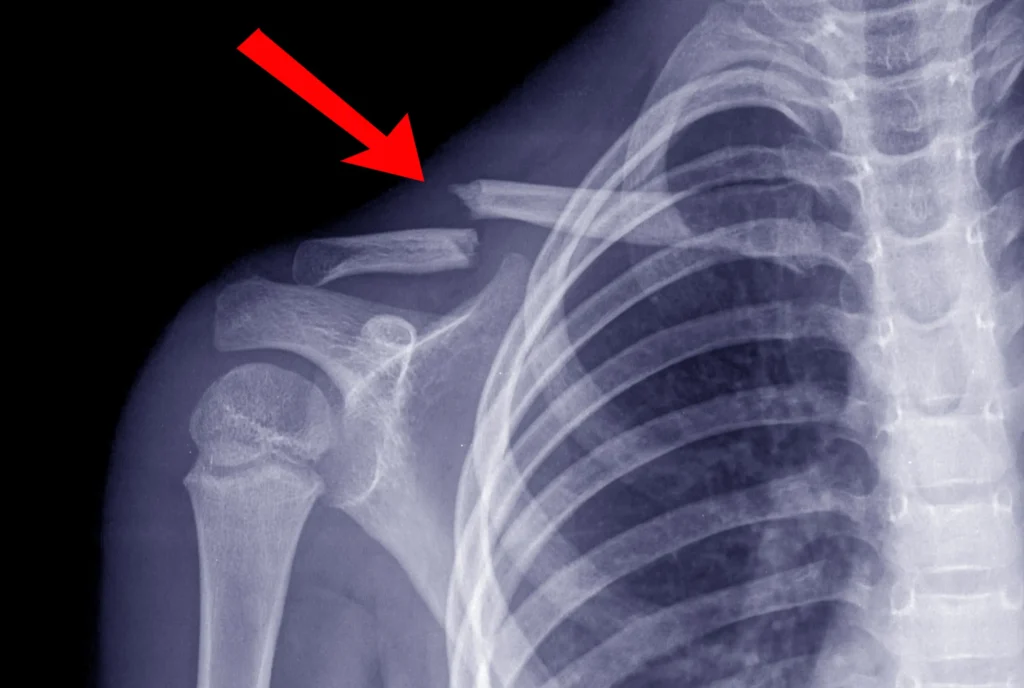

- إجراء أشعة سينية لتأكيد الكسر: تظهر الأشعة السينية مكان الكسر ونوعه، وما إذا كان هناك أي عظام مكسورة.

- إجراء فحص بالأشعة المقطعية (التصوير المقطعي المحوسب): في حالة الإصابات الأكثر تعقيدًا، أو هناك أكثر من إصابة واحدة.